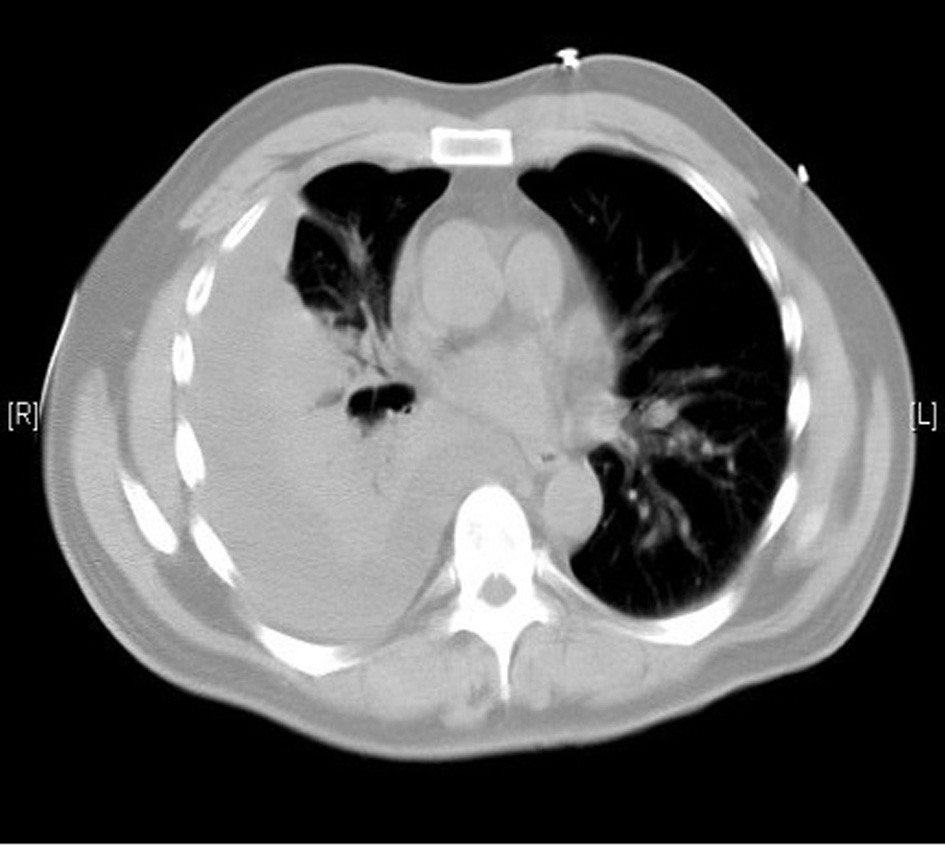

A 55-year-old previously healthy Caucasian male was referred to us for worsening right-sided pleural effusion. He was seen 1 week prior to presentation in the emergency department (ED) of an outside hospital for shortness of breath and cough, diagnosed with right lower lobe pneumonia with mild pleural effusion and discharged home on oral levofloxacin. One week later, he went to see his primary doctor for worsening symptoms who sent him to the ED. Upon presentation, the patient was complaining of worsening shortness of breath, persistent cough, right-sided pleuritic chest pain, generalized weakness, intermittent low-grade fever and chills. Chest X-ray done in the ED revealed right pleural effusion, which was confirmed by CT scan (Fig. 1, 2).

![]() Click for large image | Figure 2. Moderate right pleural effusion. |